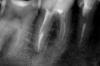

juli63 Опубликовано 4 мая, 2011 Поделиться Опубликовано 4 мая, 2011 другие зубы лечить можно. 28 мая еще не было . а каналы в 46 зубе перелечить надо.вижу кариес в 47-то же может беспокоить. Ссылка на комментарий

KNYAZ Опубликовано 14 мая, 2011 Поделиться Опубликовано 14 мая, 2011 значит беспокоит вас какой-то соседний зуб Как кто-то уже сказал судя по снимку 7-ой Советую 6-ой зуб оставить в покое до тех пор пока не разберётесь с тем зубом который беспокоит в данный момент а потом посмотрим А и ещё вам лечили зуб вообще в частной стоматологии? что-то как-то с пломбировкой подозрительно хотя всякое может быть Вообщем лечить нужно эти зубы в част стомат и у хороших спецов И когда приходите на приём ставьте доктору задачу типа"мне нужно хорошо запломбировать каналы" а если не будет получаться пломбировка как надо пусть обьяснят почему либо вообще ничего не делают Ссылка на комментарий